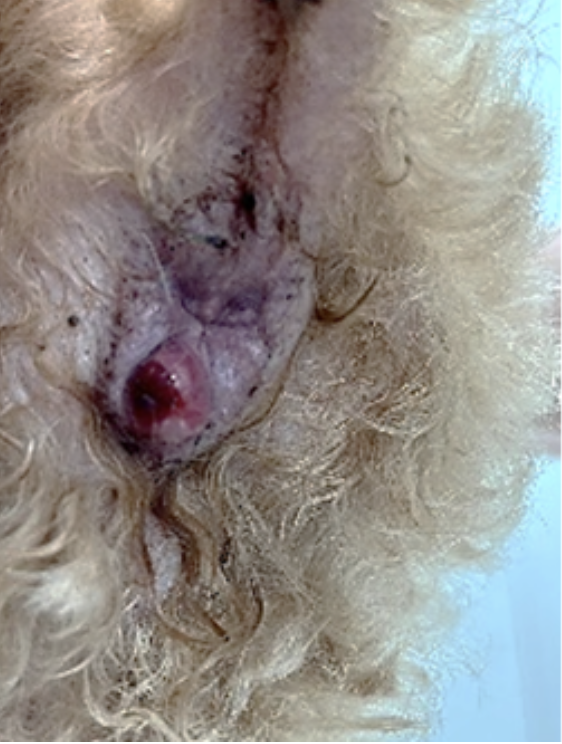

2022.12.21

症例紹介のページに肩関節脱臼の整復術について追加しました。トイプードルなどの犬種で比較的多発する疾患で、治療法が確立されておらず関節固定になるケースが多いですが、靭帯再建術で良好に経過することも多いです。前肢を跛行するなどの症状がある場合はご相談ください。